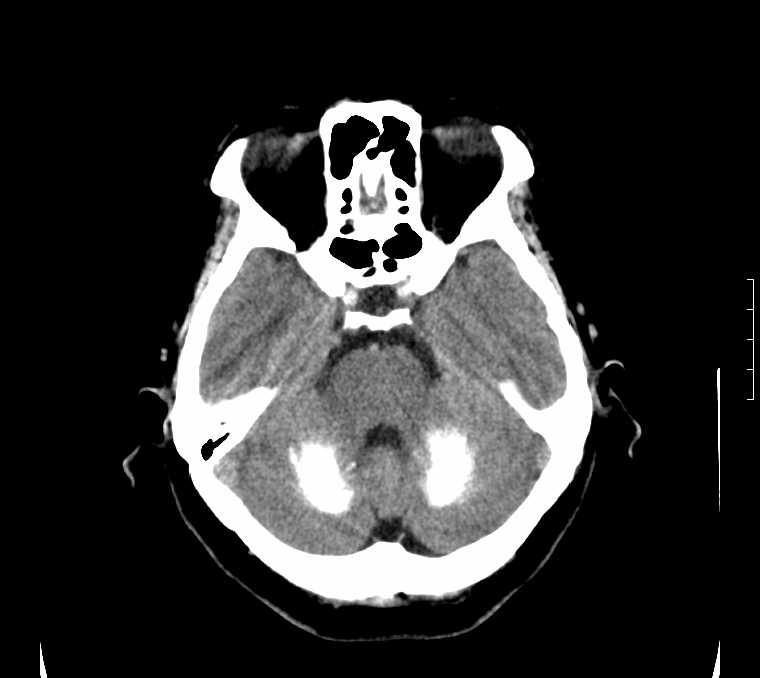

标题: CT24387:看看这例脑部改变!!

老年女性。头晕。

考虑:甲旁减。

fahr病

鉴别于特发性家族性脑血管亚铁钙沉着症(fahr`s病)与甲状旁腺机能低下之间,请结合临床及相关实验室检查。